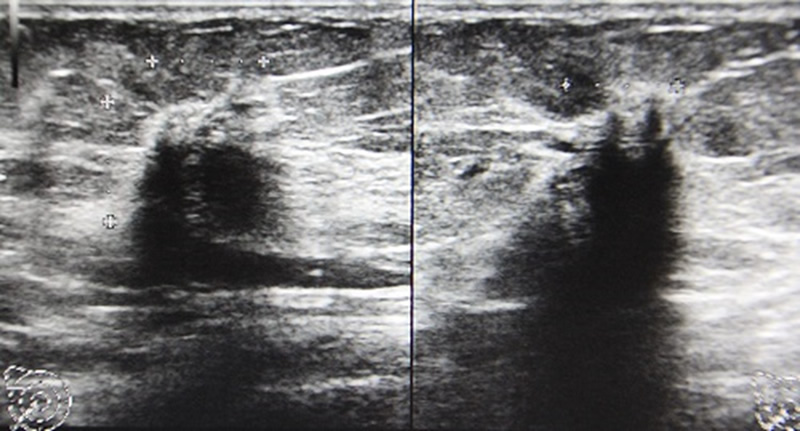

乳がんを診断する方法として、マンモグラフィと超音波の2つがあります。

一方、超音波での検診は現時点では自費診療となります。 (乳房に腫瘤を触れる、乳頭から血が出るという症状がなく、漠然と心配なので検診してほしいという場合)超音波での検診のデータとしては、厚生労働省が国家的プロジェクトとして立ち上げたJ-START(ジェイ・スタート)という乳がん検診の比較試験があります。40歳以上の女性で、マンモグラフィと超音波検査を併用する検診と、併用しない検診(マンモグラフィのみ)を比較して死亡率が併用群で下がるかどうか観察する試験ですがまだ最終結果はでていません。途中経過として併用群で乳がんの検出率があがったとの結果がでていますが、要精密検査の率もあがっており、解釈にはまだもう少し時間が必要です。